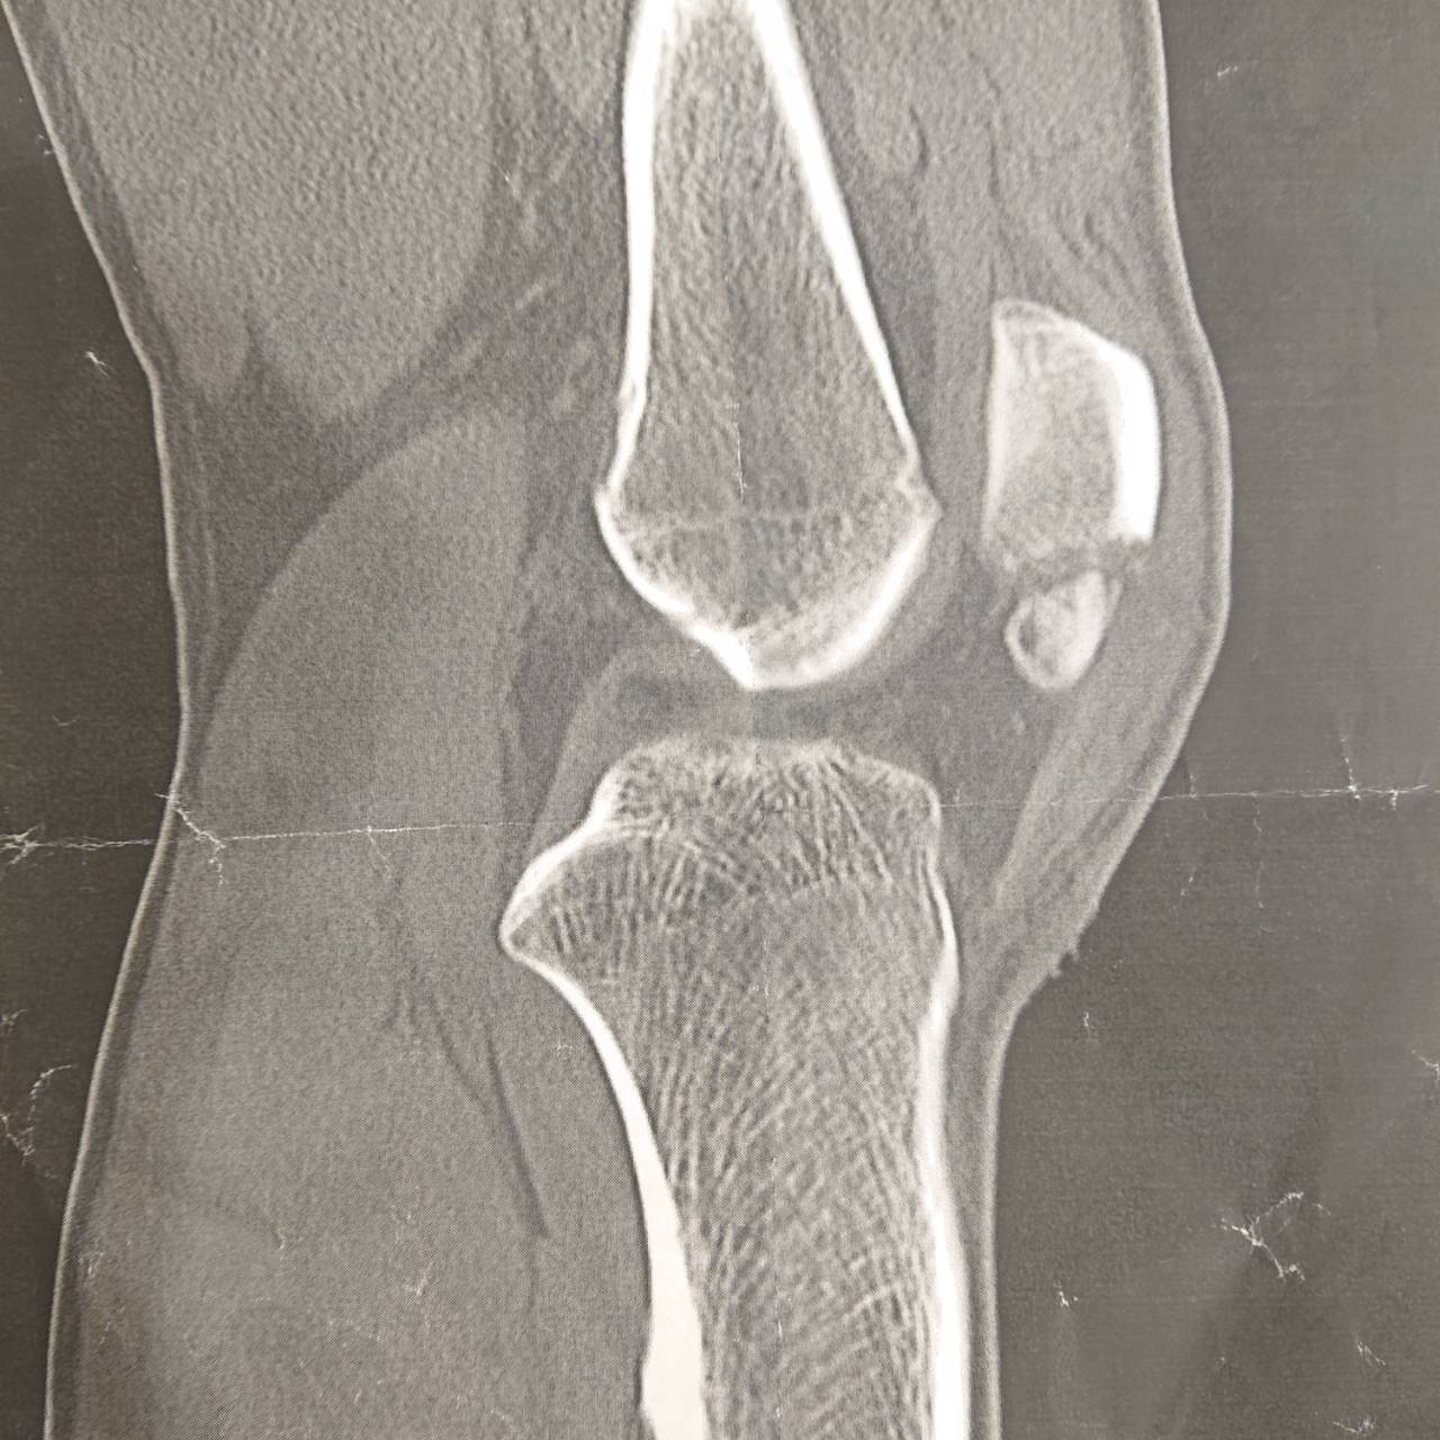

ただ、左膝蓋骨、膝のお皿ですね。こちらを粉砕骨折しまして、手術をして18日間入院後、今はリハビリに励んでいます。

そこで、『あー、膝のお皿粉々ですね』と診断され、手術が必要だと言われましたが、家も職場も渋谷だと伝えると、なら東京の病院に入院して手術してもらってくれということになりました。